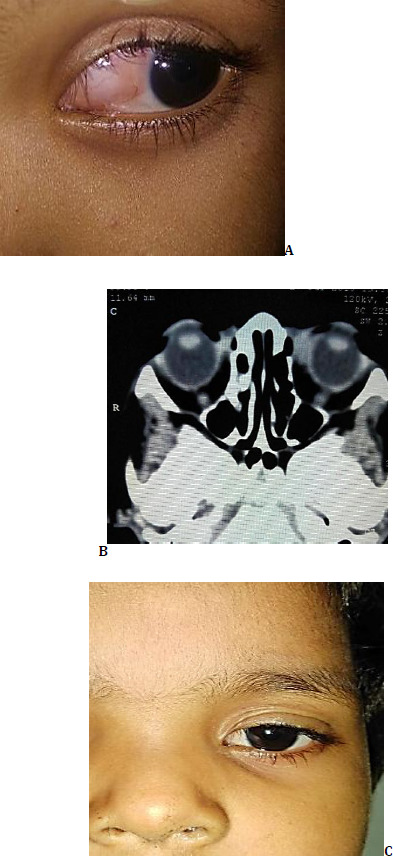

眼眶静脉淋巴畸形或淋巴管瘤是眼眶的脉络膜瘤。常见于儿科人群,病变是臭名昭著的扩散到各种解剖空间,由于其浸润性。此外,血管的性质也给完全切除带来了挑战。出血在病变中并不罕见,这可能导致永久性的眼功能受损。医疗管理包括向病变的囊性区域注射硬化剂,导致收缩和塌陷,然后完全切除,这是最合适的治疗选择。作者提出了一系列的情况下,其中淋巴管瘤已完全切除使用这种最小的操作方法。

Orbital venous lymphatic malformations or lymphangiomas are choristomas of the orbit. Common in the pediatric population, the lesion is notorious for spreading into various anatomical spaces due to its infiltrative nature. Additionally, the vascular nature poses challenges to complete removal. Hemorrhages are not uncommon in the lesion, which may result in permanently compromised ocular function. Medical management involves injecting sclerosant into the cystic areas of the lesion, resulting in shrinkage and collapse, followed by total excision, which is the most suitable treatment option. The authors present a series of cases in which lymphangiomas have been completely excised using this minimal manipulative approach.